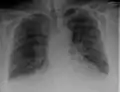

Chest X-rays are frequently used to aid in the diagnosis of CHF. In a person who is compensated, this may show cardiomegaly (visible enlargement of the heart), quantified as the cardiothoracic ratio (proportion of the heart size to the chest). In left ventricular failure, evidence may exist of vascular redistribution (upper lobe blood diversion or cephalization), Kerley lines, cuffing of the areas around the bronchi, and interstitial edema. Ultrasound of the lung may also be able to detect Kerley lines.[69]

Congestive heart failure with small bilateral effusions